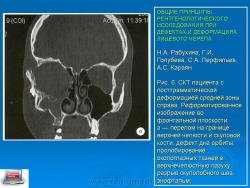

Рис. 6. СКТ пациента с посттравматической деформацией средней зоны справа. Реформатированное изображение во фронтальной плоскости:

а — перелом на границе верхней челюсти и скуловой кости, дефект дна орбиты, пролобирование окологлазных тканей в верхнечелюстную пазуху, разрыв скулолобного шва, энофтальм;

б - СКТ того же пациента после операции. Реформатированное изображение в боковой проекции. Устранение энофтальма с помощью костного трансплантата, замещающего дно орбиты. Видна деформация зрительного нерва и нижней глазодвигательной мышцы;